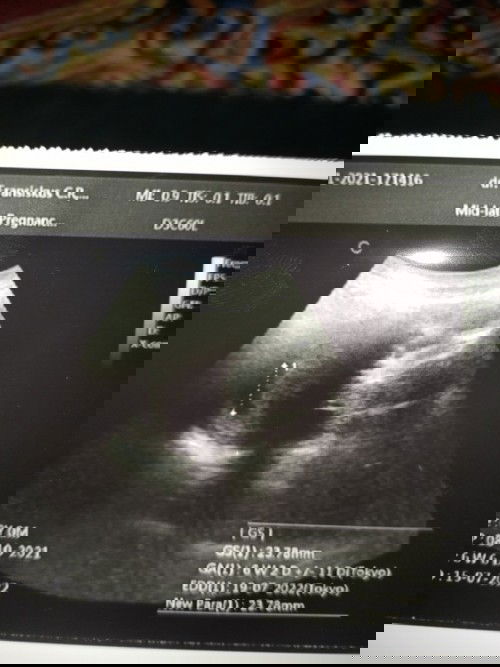

hasil pemeriksaan USG

bun mau nanya.. ini tadi saya USG kehamilan 6 minggu 5hari , masih kantung saja... apakah ada yang sama bun??